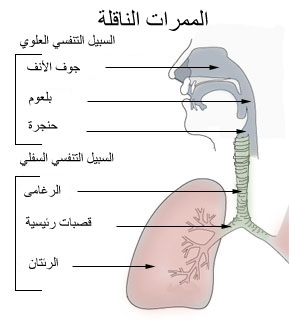

جوف الأنف أو الحفرة الأنفية إنگليزية: Nasal Cavity هو الجزء العميق من الأنف والممتد من المنخرين في الأمام وحتى المنعرين في الخلف[1][2]، أي حتى البلعوم في الخلف.[3] يقسم جوف الأنف إلى قسمين أيمن وأيسر بواسطة بنية عظمية غضروفية تدعى حاجز الأنف أو الوتيرة.[1]

الدور التنفسي

جوف الأنف هو أول أجزاء السبيل التنفسي، ويعتبر التنفس عن طريق الأنف أفضل من التنفس عن طريق الفم؛ فالتوعية الغزيرة لجوف الأنف وأشعار الدهليز والإفرازات المخاطية تساهم بتصفية الهواء المستنشق وتدفئته وترطيبه وتسمى هذه العملية الثلاثية (التصفية، التدفئة، الترطيب) بتكييف الهواء.

يحتوي جوف الأنف في أجزائه العلوية على مستقبلات حسية خاصة بحاسة الشم، ولذلك يعتبر الأنف من أعضاء الحواس.

يقوم جوف الأنف بالإضافة لدوريه التنفسي والشمي بعملية تنظيف ذاتية تتيح له التخلص من الجسيمات الأجنبية التي اقتنصها من الهواء وذلك عن طريق حركة الأهداب نحو البلعوم حيث يتم بلعها.[1].[4][5]